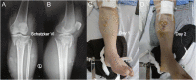

Background: Acute compartment syndrome (ACS) is an orthopedic emergency that commonly occurs after severe tibial plateau fracture. Fracture blisters form on the skin, and it was found in our previous study that when blisters form, the compartment pressure significantly decreases. However, the potential mechanism underlying this pressure decrease has not yet been elucidated. Methods: To obtain a comprehensive understanding of the changes that occur after blister formation on the skin, the changes in tight junction expression in the skin after tibial plateau fracture were observed. Blister samples and normal skin were collected from patients with bicondylar tibial plateau fractures with or without blisters. The epidermis thickness was measured, and the difference in the levels of K1, K5, K10, and skin barrier proteins such as claudin 1, claudin 2, and occludin between the two groups was evaluated by immunochemistry analysis, immunofluorescence, Western blotting, and qPCR. Results: The skin was thinner and the levels of K1, K5, and K10 were significantly decreased in blistered skin. Furthermore, the PI3K/AKT pathway was found to be activated, and the tight junction expression was significantly decreased in blistered skin. This indicates that the paracellular pathway, which is essential for accelerating fluid accumulation in blisters and indirectly decreases compartment pressure, was activated. Conclusion: Changes in the tight junction expression after blister formation may underlie blister fluid formation and indirectly explain the decrease in compartment pressure under blistered skin after severe tibial plateau fracture.